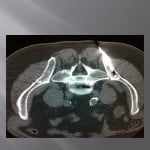

Biopsie sous guidage scanner